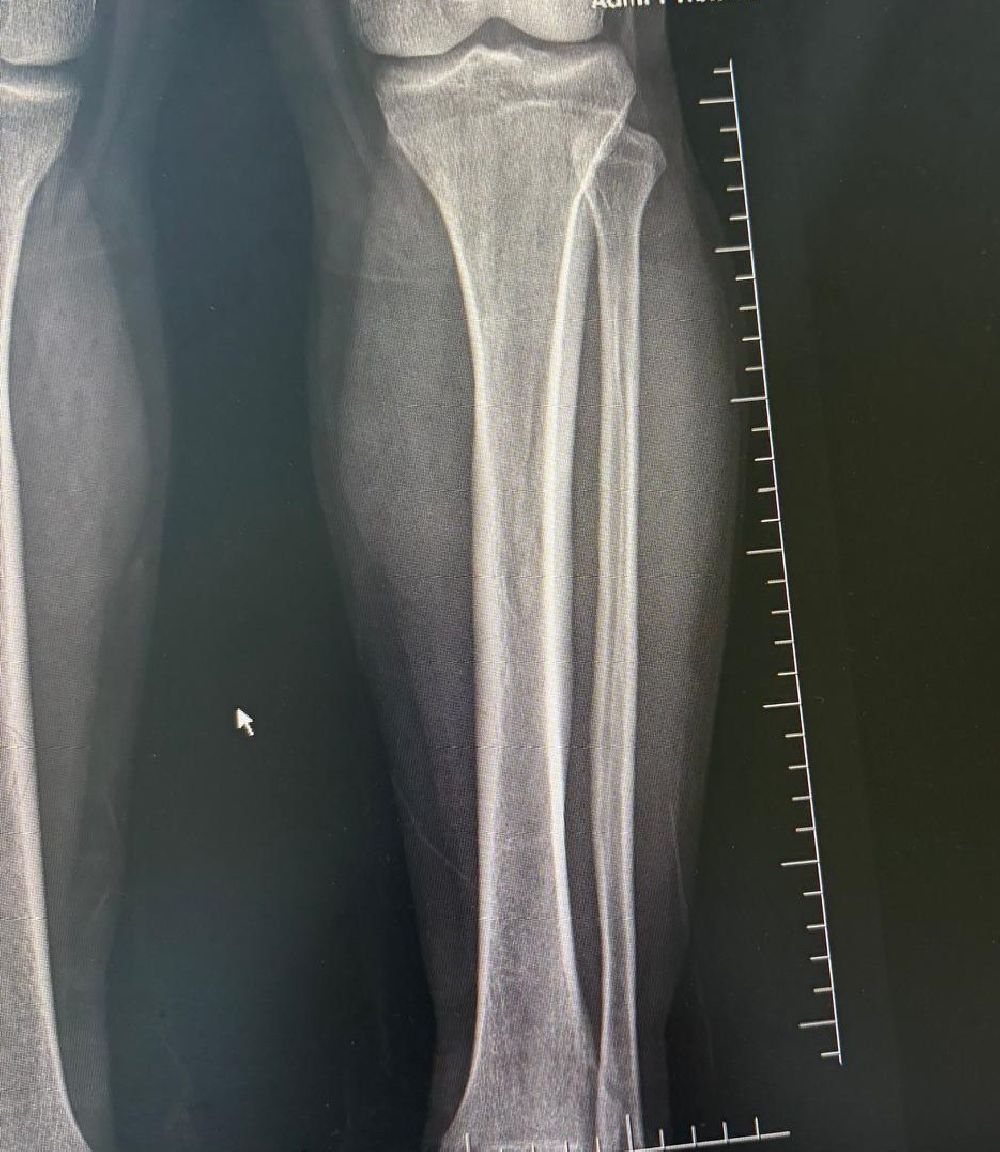

Denizli'de yaşayan 39 yaşındaki M.G., boyunun 1.58 olmasından kaynaklı fiziksel ve bedensel sorunların yaşadığını, daha uzun bir görünüme kavuşmak ve yaşam kalitesini artırmak amacıyla Denizli Özel Tekden Hastanesi'ne başvurdu. Hasta uzun yıllardır boyunun kısalığının gerek günlük yaşamda gerekse sosyal çevresinde çeşitli zorluklara yol açtığını dile getirdi. Aynı zamanda duruş bozukluğu ve bazı fiziksel rahatsızlıklar nedeniyle uzman bir hekime danışma kararı alan M.G., hastanenin Ortopedi ve Travmatoloji bölümünde görev yapan iki uzman doktora başvurdu. Ortopedi ve Travmatoloji Uzmanı Prof. Dr. Mahmut Argün ve Op. Dr. Necip Özateş tarafından detaylı şekilde muayene edildi. Doktorlar tarafından yapılan değerlendirmeler sonucu, hastanın ortalama 10 santimetre daha uzamasının mümkün olduğu belirtildi.

Ameliyat aşamasının ardından gerçekleşen süreci tek tek dile getiren Ortopedi ve Travmatoloji Uzmanı Prof. Dr. Mahmut Argün, "Hastamız 1.58 boyunda olması nedeniyle sürekli boyunun kısalığından dolayı hem fiziksel hem de bedensel rahatsızlıkların olduğunu dile getirdi. Israrla boyunun uzatılmasını bizden talep eden hasta 2 aşamalı olunması gereken muayeneyi 1 aşamalı olmasını istedi. Sol tarafından başlayarak hem femur hem de tibia 5 ila 6 santimetre arasında uzatmayı planladık. Hastamızı ameliyata alıp bu işlemleri gerçekleştirdik. Hasta şuanda uzatma işlemlerinin yapılabilmesi için malzeme yerleştirme aşamasını gerçekleştirdik. Ameliyattan 10 gün sonra uzatma işlemlerini başlayacağız. Uzatma işlemleri yaklaşık 60 gün sürecek. Uzatma işlem süreci geçtikten sonra işlemi durdurup kaynaması için 2-3 ay bekleyeceğiz. Ardından ise hastanın üzerinden malzemeleri yaklaşık 150-200 gün arasında çıkaracağız. Bu tarz işlemler meşakkatli ve özen isteyen ameliyatlar" diye konuştu.

Uzama sürecinde her gün 1 milimetre olmak üzere kurulan mekanizmanın başladığını dile getiren Ortopedi ve Travmatoloji Uzmanı Op. Dr. Necip Özateş, "Her gün 1 milimetre olmak üzere, üzerindeki mekanizma üzerinden hem uyruk kemiği hem kaval kemiği uzatılmaya başlıyor. Hem bu şekilde kemik uzaması hem de bu esnada kemik kaynaması aynı anda olduğu için daha kontrollü bir işlem oluyor. Hedef uzunluğa ulaştığımızda uzatma işlemini sonlandırıyoruz. Sonrasında da kemiğin kaynaması sürecine geçiyoruz" dedi.